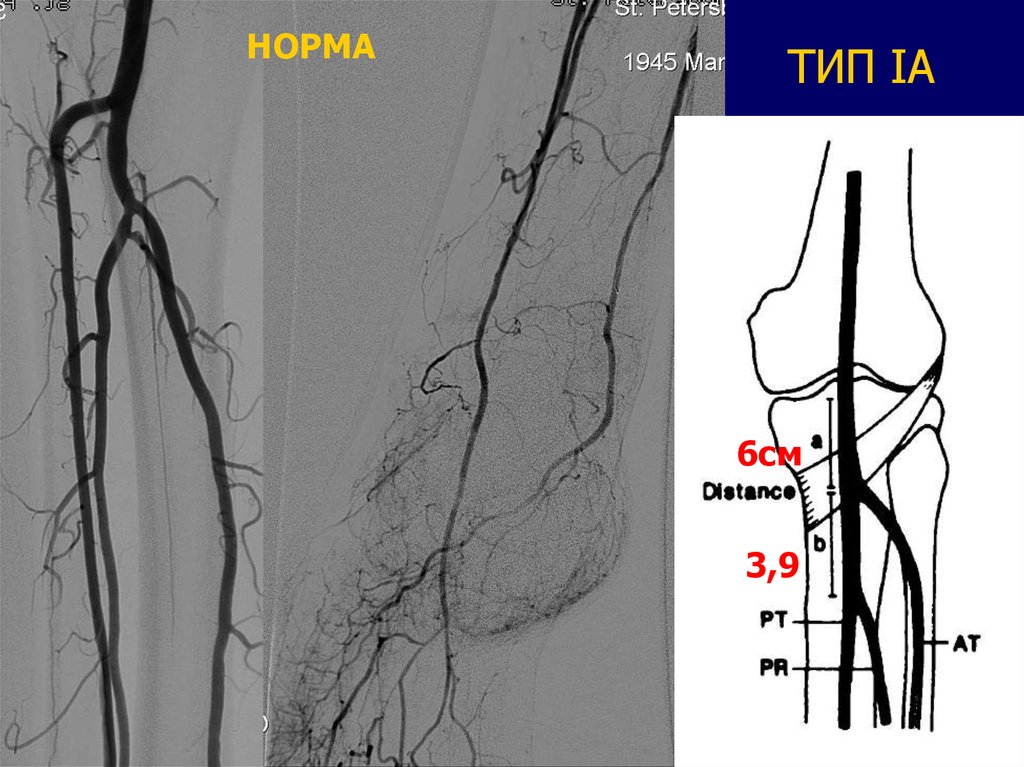

20.

НОРМА

ТИП IA

6см

3,9